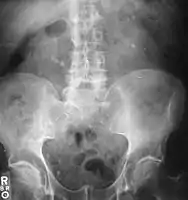

Otherwise a noncontrast helical CT scan with 5 millimeters (0.2 in) sections is the diagnostic method to use to detect kidney stones and confirm the diagnosis of kidney stone disease.[13][47][51][52][7] Near all stones are detectable on CT scans with the exception of those composed of certain drug residues in the urine,[53] such as from indinavir. Calcium-containing stones are relatively radiodense, and they can often be detected by a traditional radiograph of the abdomen that includes the kidneys, ureters, and bladder (KUB film).[53] Some 60% of all renal stones are radiopaque.[51][54] In general, calcium phosphate stones have the greatest density, followed by calcium oxalate and magnesium ammonium phosphate stones. Cystine calculi are only faintly radiodense, while uric acid stones are usually entirely radiolucent.[55]

- Bilateral kidney stones can be seen on this KUB radiograph. There are phleboliths in the pelvis, which can be misinterpreted as bladder stones.